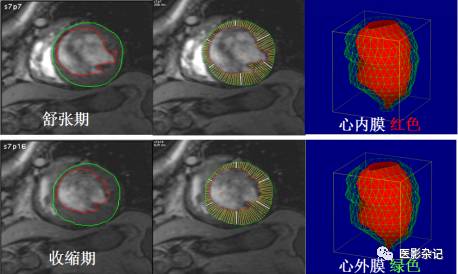

其中,心脏功能学检查是MRI的一项重要应用,其过程大致为:采用电影采集扫描获取并显示心脏MRI心脏动态图像,也就是在一个心跳周期中的多个时相的心脏三维影像;采用手动、半自动或全自动方式勾画心室内外侧壁最大舒张末期和最大收缩末期轮廓,如果能够勾画整个心动周期舒收的每一时相更好;通过勾画的轮廓用心功能分析软件包计算出心室容积、肌块和心功能有关参数绘出心室容积及容积的变化率曲线图;从而进一步根据心室内外心肌壁的轮廓变化来分析及评价心肌厚度,并且以图、表形式显示心肌厚度的变化。

*图片来自北大医院影像科李沙